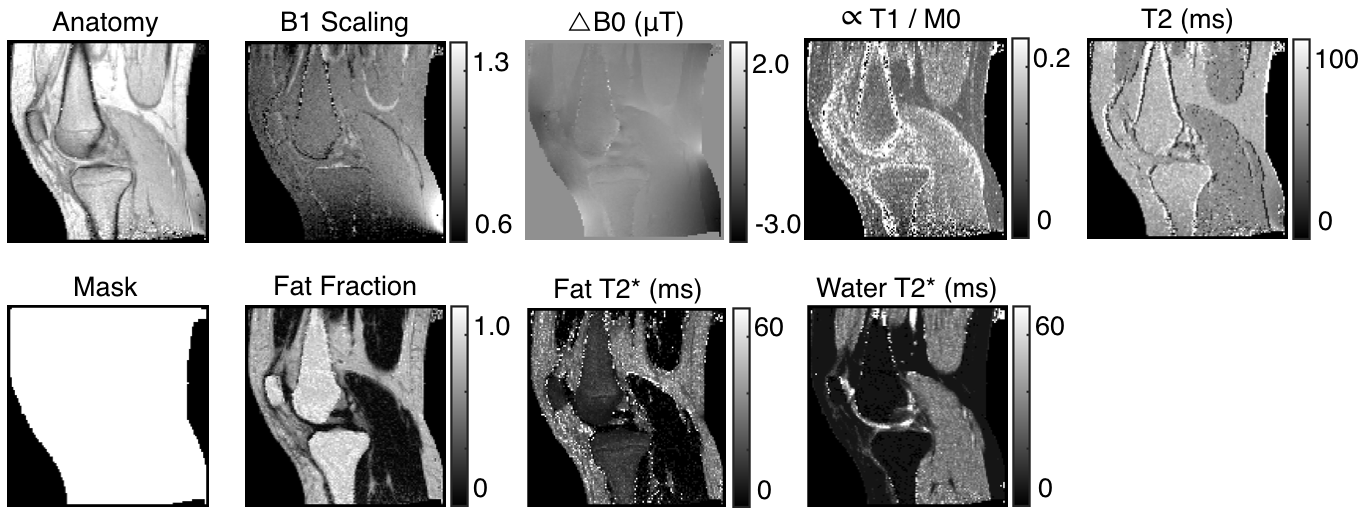

Images of a sagittal slice of a knee of size were collected with a kHz receiver bandwidth with a kHz receiver bandwidth and a mm slice thickness. The field of view was cm. The MR machine’s body coil was used for excitation, and an extremity coil was used for reception.

For imaging the knee, the multiMap sequence used had a TR of ms and a of ms. The mask accurately isolates those pixels corresponding to tissue. Under the assumption that was long enough to accurately distinguish estimates of and , we also presented imagery. The fat and muscle show different values, as expected. The quantity in the cortical bone is high due to the short leading to a near signal in this region in image . The fat fraction shows increased signal intensity in the fat and bone marrow, as expected.